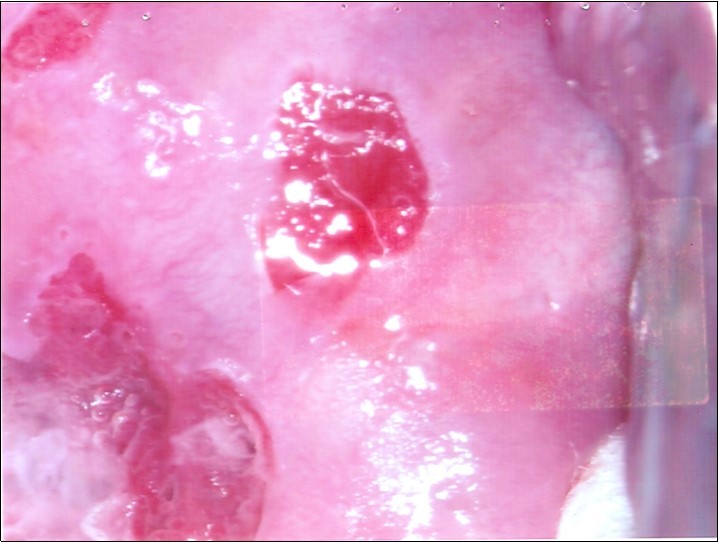

Repeat colposcopy was performed after 6 weeks. This revealed a small ulcerated area at the site of previous biopsy with rolled healing edges, and a separate small ulcer at the 12 o’clock position. (Figure 2a, Figure 2b, Figure 2c) Careful inspection of the buccal mucosa revealed similar ulcers in the left buccal region. (Figure 3)

Figure 2b.Repeat colposcopy (high magnification)

Figure 2c.Repeat colposcopy (high magnification)